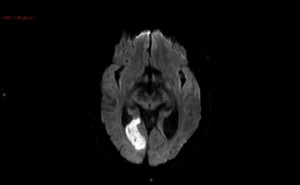

Figure: The figure shows a diffusion weighted MRI scan in a patient with posterior circulation stroke. We are designing pilot intervention studies for stroke patients to assess the feasibility of clinical outcome studies of novel neuroprotectant therapies.